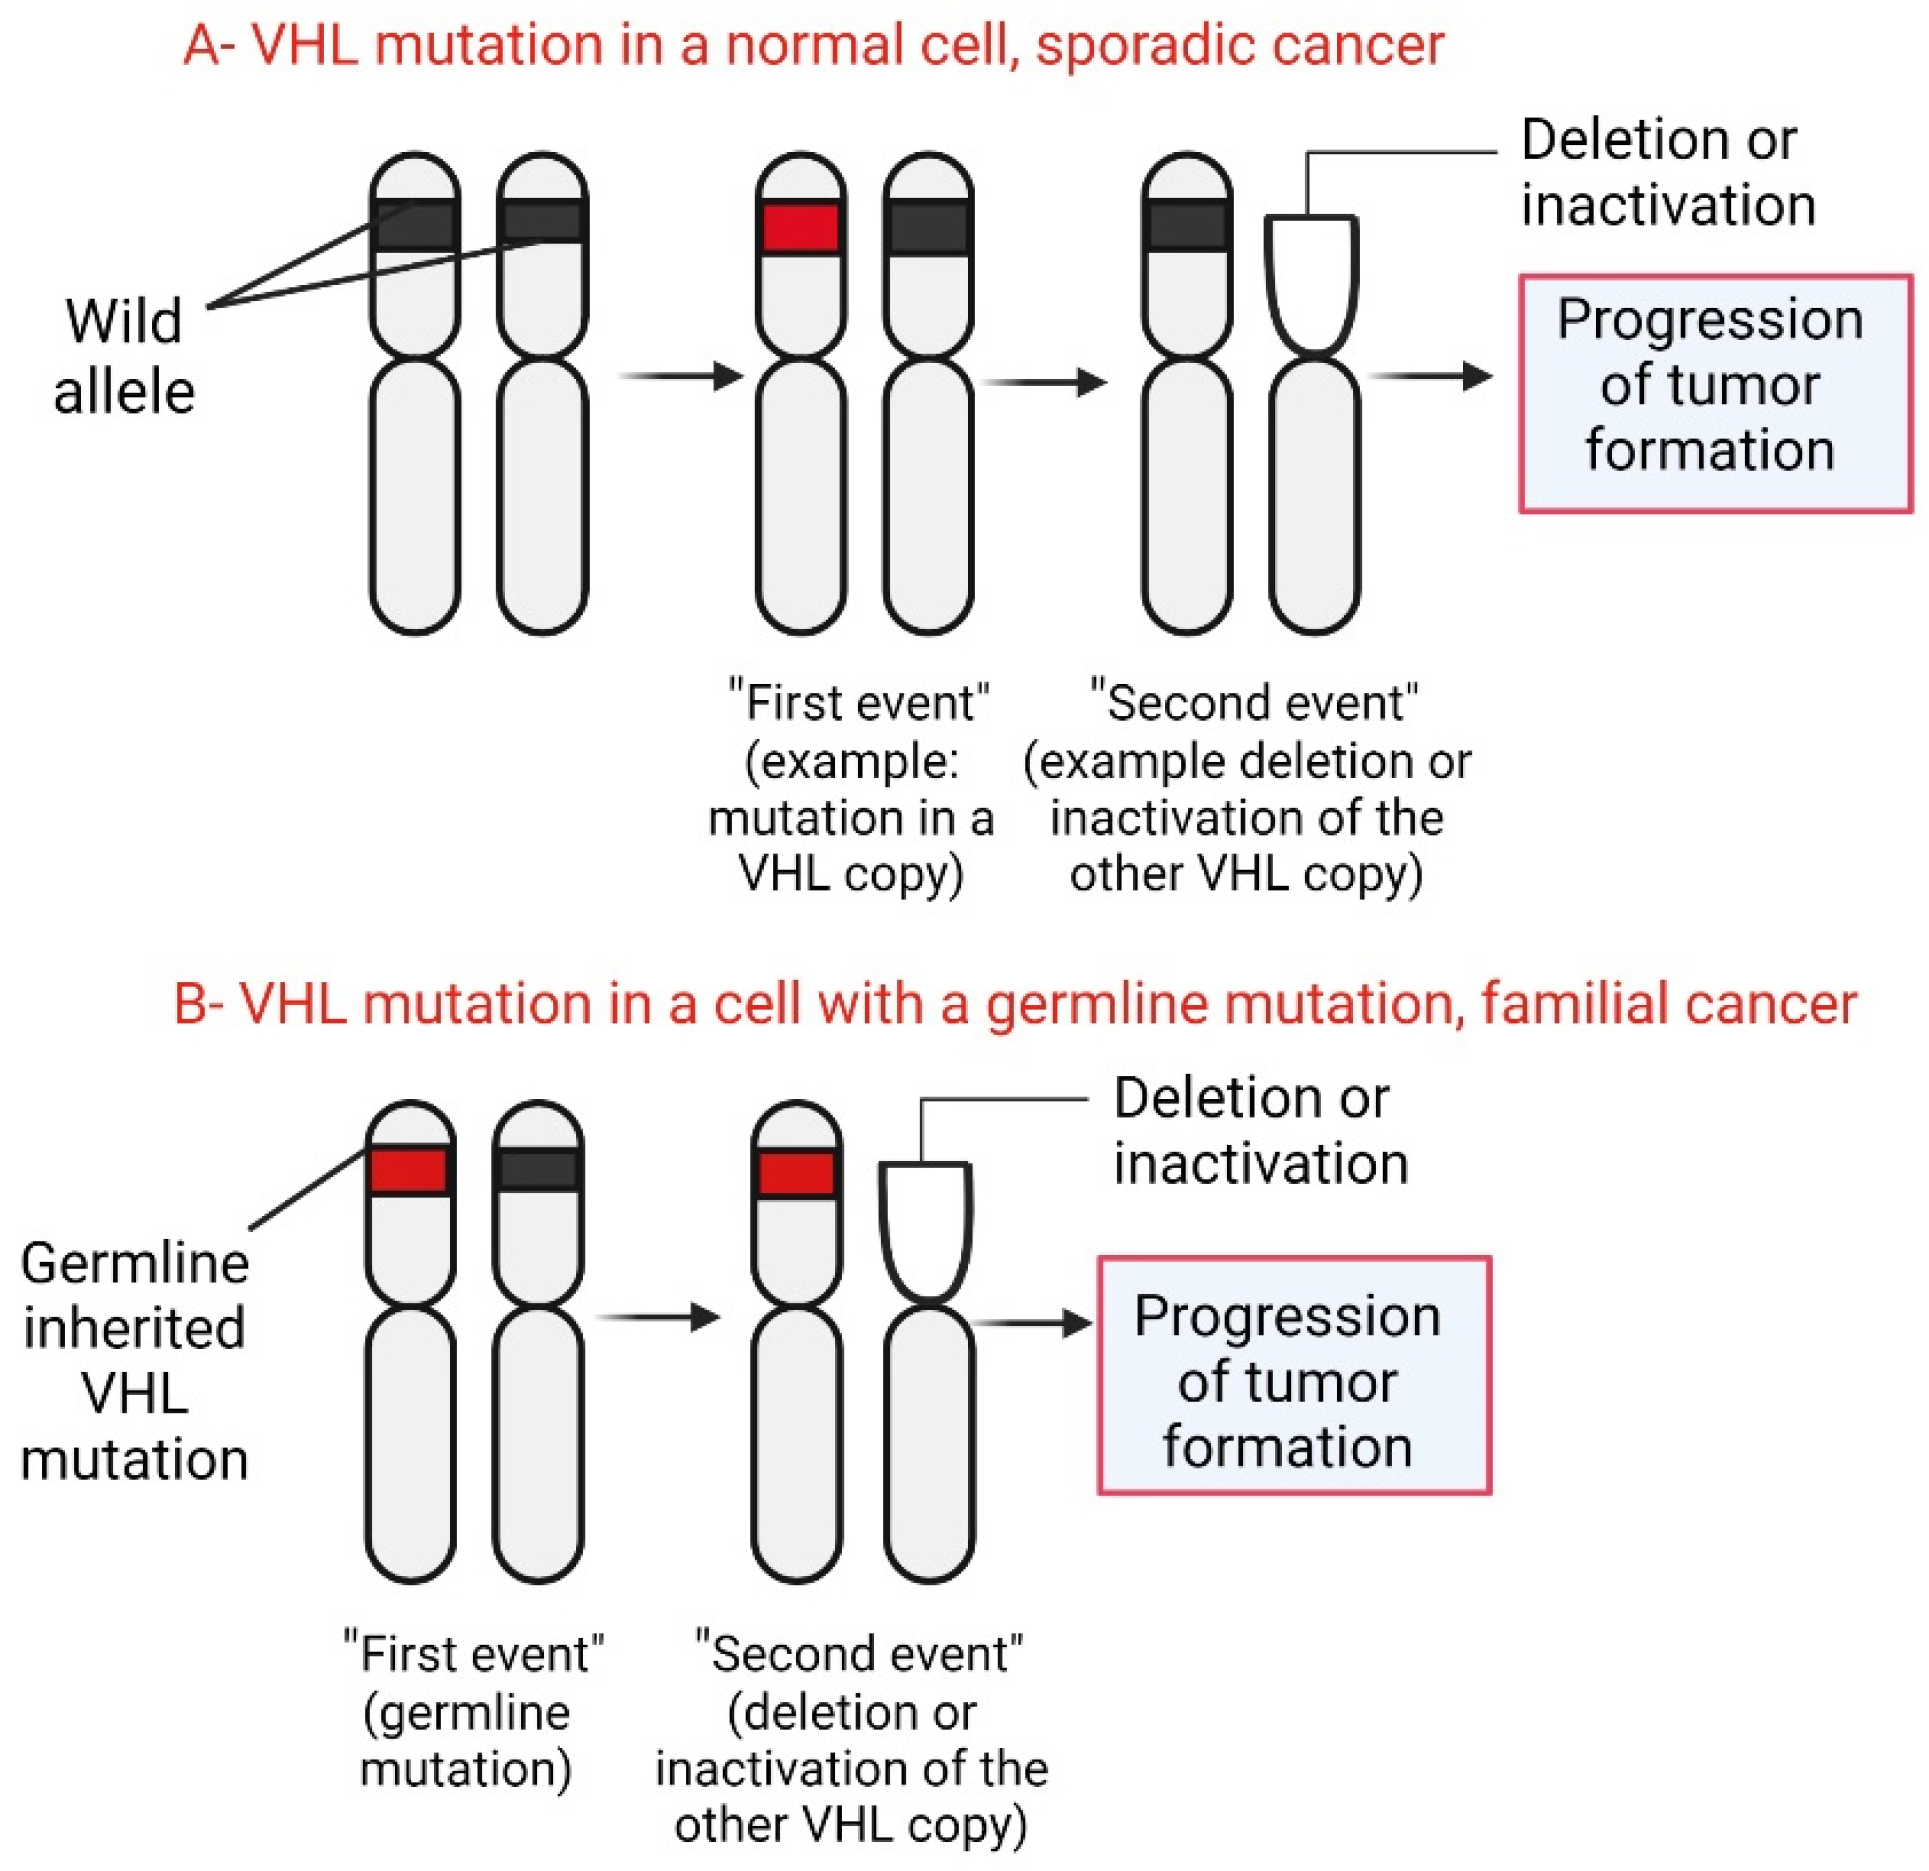

3.3. Mutations